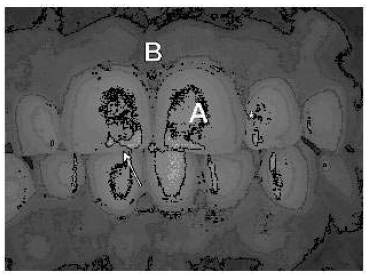

Com base na fotografia clínica frontal mostrada acima, julgue os itens a seguir.

A seta aponta para a borda oclusal do incisivo central.